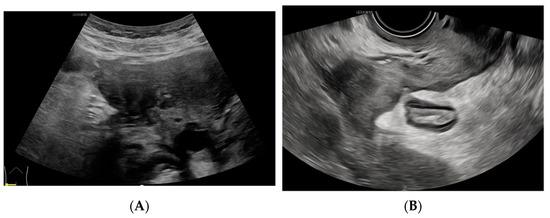

Figure 2. Positron emission tomography–computed tomography (PET-CT) reveals an irregular high-density mass in the pelvic mesentery, forming a ‘C’ shape enveloping the sigmoid colon from the right, with unclear demarcation from the sigmoid colon and markedly increased FDG uptake. FDG can be used as an important indicator to distinguish benign and malignant lesions by reflecting the level of glucose metabolism in the lesion, but it does not have absolute specificity. Tuberculosis and inflammatory lesions can also show increased FDG. There may be chronic granulation tissue hyperplasia near actinomycete abscesses or sinuses, and the infiltration of various inflammatory cells, tissue cells, and fibroblasts, resulting in high uptake of 18F-FDG.

Diagnostics 14 01923 g002